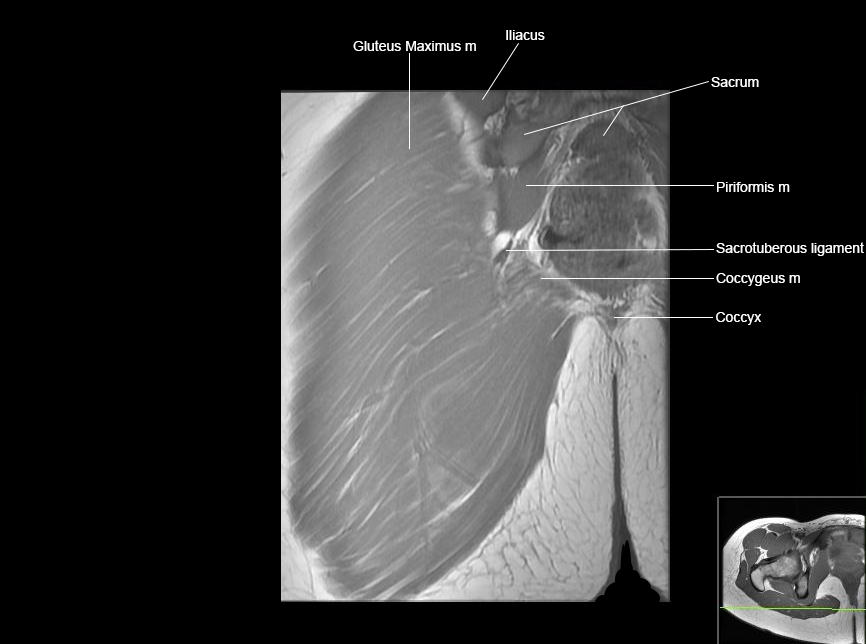

Hip

Basic Hip MRI

MRI Hip Anatomy

Scroll using the mouse wheel or the arrows